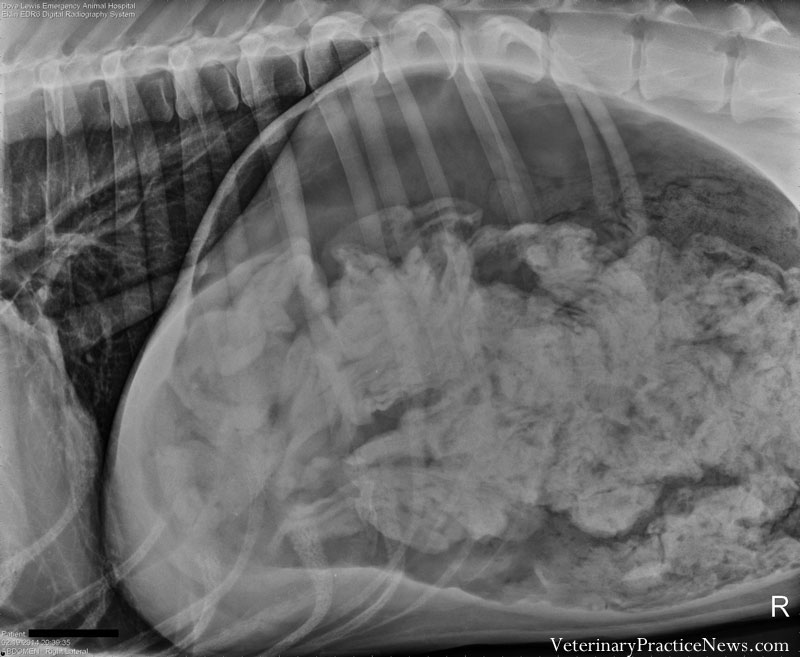

季軍:吃掉43.5隻襪子的的大丹狗

這隻3歲的大丹狗因為不停的嘔吐被主人帶去獸醫院,X光結果顯示牠的胃嚴重擴張並有大量異物,在獸醫師為牠進行手術時才發現這些異物是襪子!牠總共吞了43.5隻襪子,聽起來很可怕,不過這隻狗狗在手術完成後第二天就可以出院回家了。